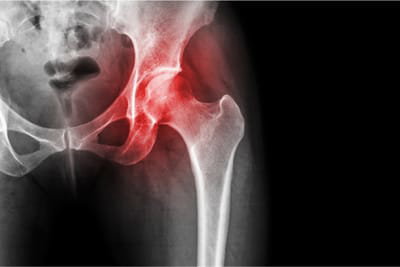

Durerea la sold este termenul general pentru durerea resimtita in sau in jurul articulatiei soldului. Nu se simte intotdeauna la nivelul soldului in sine, dar in schimb poate fi simtita in zona inghinala sau a coapsei.

Soldul este una dintre cele mai mari articulatii care sustine greutatea corpului, motiv pentru care durerea de sold este atat de comuna.

Durerea de sold poate fi simtita in multe zone conexe ale corpului, inclusiv coapse, zona inghinala, fese si articulatia soldului. Uneori, singurul semn al unei afectiuni de sold este durerea de genunchi. Acest fapt este relativ comun si se numeste durere iradiata.

Durerea de sold se poate agrava datorita activitatii, de exemplu dupa un exercitiu fizic, o plimbare lunga sau o alergare. Este posibil sa descoperi ca flexibilitatea ta de miscare este redusa si ca nu-ti poti misca soldul sau piciorul la fel de usor ca inainte.